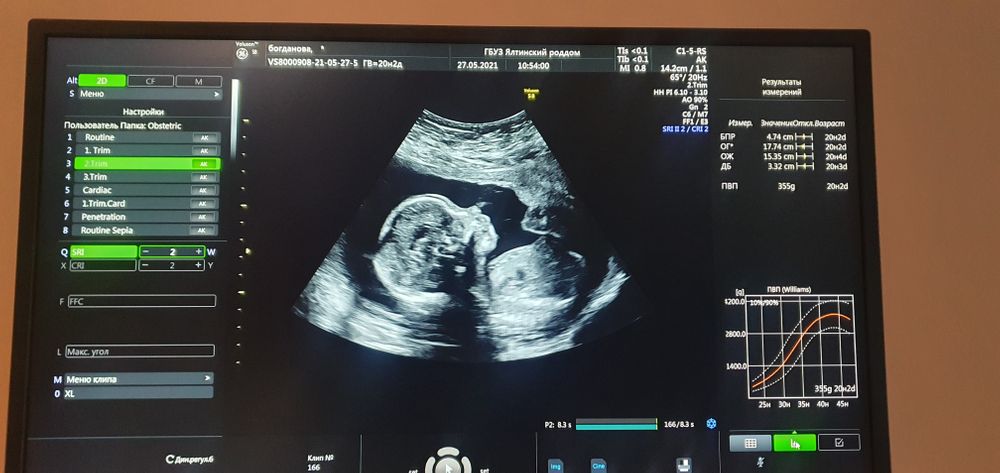

Ну и само узи порадовало))

А ещё я лишний раз убедилась, что Святослав, наш средний, обладает даром угадывать пол малышей в пузе у мамы))

Впсилису он угадал почти сразу , да и тут с полом не ошибся))) загадал братика - тот и получился)))